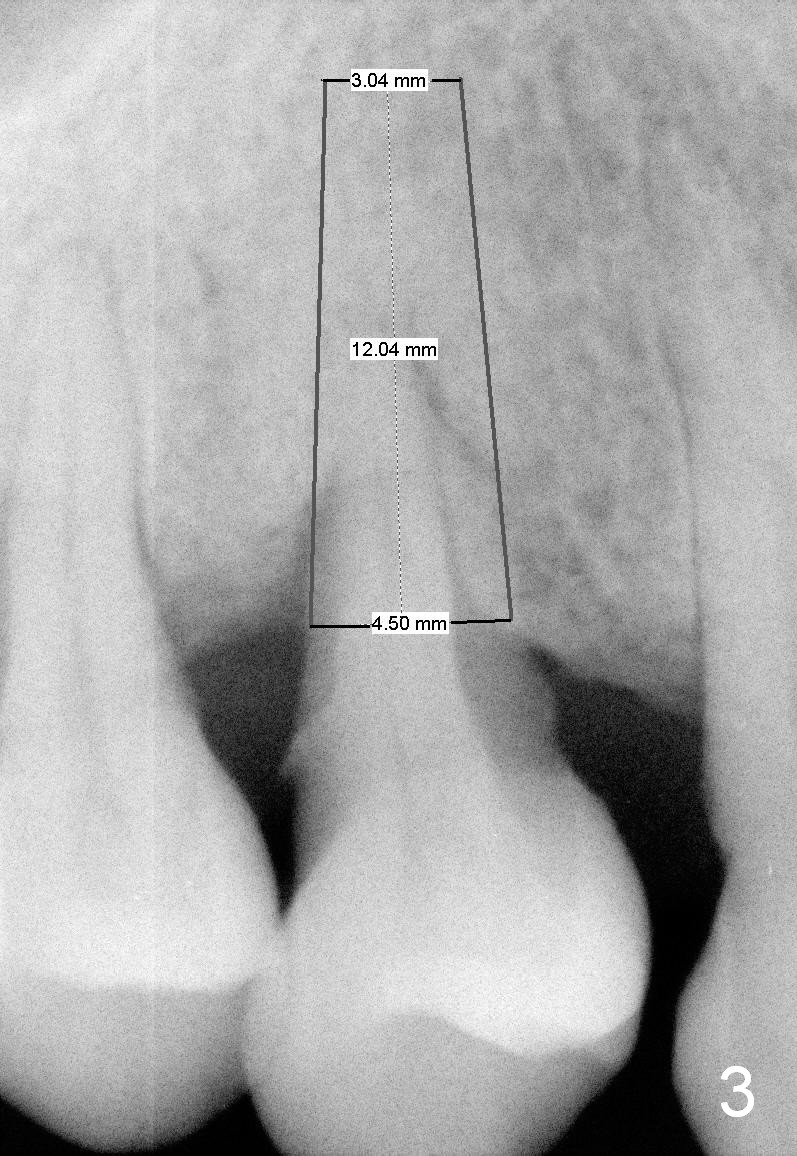

A 43-year-old lady has generalized moderate localized advanced chronic periodontits (Fig.1,2). In spite of 4 quadrant scaling & root planing, the tooth #19 develops 2 perio abscesses (Fig.4 with insertion of 2 guttae perchae); periodontal ligament spaces increases (compare Fig.2,4). It appears that the tooth is non salvageable and should be replaced with an immediate implant (Fig.5). The extraction socket will be treated with Metronidazole. A 2 mm pilot drill is used to start osteotomy in the septum (14 mm deep), followed by reamers until 3.5 mm. A 5x17 mm tap is placed to test stability. If the stability is high, place a 5.3x12 mm SM implant. If insertion torque is too high, use the corresponding drill before re-place the implant. Collagen dressing is placed in the peripheral and deep portion of the sockets, while bone graft in the top portion of the sockets (near implant threads). Use 1 or 2 amalgam carriers to deliver the graft lateral to the implant precisely so that a cover screw does not have to be placed. Next place a cemented abutment. If trajectory of the implant is correct, an abutment as large as 7.8x5(3) mm could be used (pink). Fabricate an immediate provisional. Do not over trim the margin of the provisional so that it can cover the socket completely.